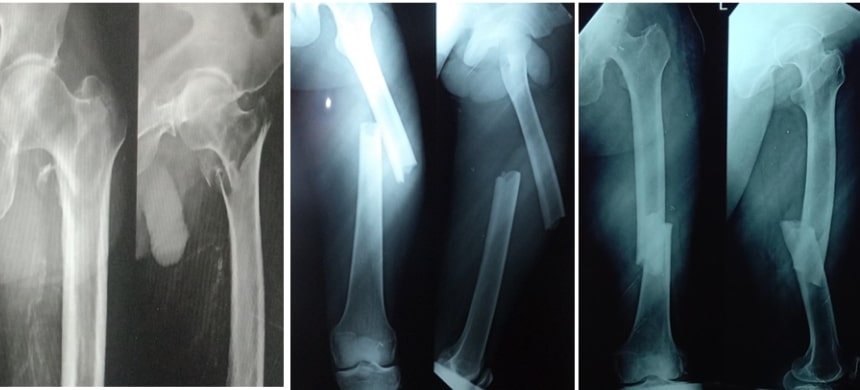

But if the fragments are displaced from each other then there is a lot of chance of non-union of the fracture. So this fracture should be fixed in the correct anatomical position. This kind of fixation needs the use of plates, screws etc. If we fix the fragments in good anatomical position and if the bone fragments get very good blood supply then the fracture will unite very well.

If a displaced fracture comes out of the skin or the fracture fragment is piercing the skin and coming out of the internal environment it is called an open fracture. This kind of open fracture has got a high risk of getting an infection because it is exposed to the external environment which contains dust, soil and bacteria. So, this contaminated fracture has got a lot of chances for going for non-union that means not getting united. So, this kind of open fractures need debridement for cleaning of the wound as well as cleaning of the fracture site and fixation of the fracture using modern implants or fixators. These open fractures need very good care so that in these kinds of situations we do keyhole surgeries also.

Making a small hole and fixing the fractures through the small hole by using plate, screws or nails is called minimally invasive surgery or keyhole surgery. As we are not opening the fracture site, we are not damaging any muscles, nerves or blood vessels around the fracture. We keep the internal environment of the fracture intact. So, the healing of the fracture will be quick and there is no loss of blood in this kind of Keyhole surgeries. The invention of C arm machines and the latest surgical equipment's made keyhole surgeries possible in orthopaedic field.

Most of the fractures of the leg bones are operated and fixed using this keyhole surgery. Most of the fractures of arm and forearm are fixed with plate and screws. Intra-articular fractures are the fractures involving the articular surface of bones. They need to be reconstructed properly. They should be fixed with proper implants. This fixation is very important to get back the moments of any joint.